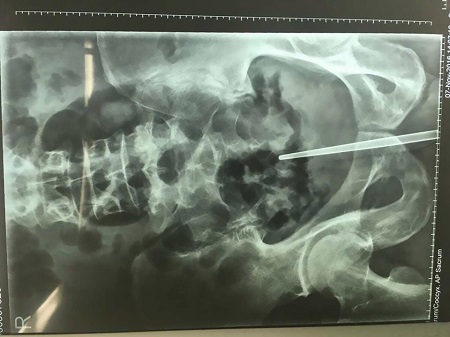

A horrific X-ray from the hospital revealed how deep the chopstick ended up

A stomach-churning scan shows the chopstick protruding from the man’s body, before Chen went under the knife to have it surgically removed.

The operation was a success but Doctor Ruan Zhixian, who performed the operation, said the chopstick had reached the man’s rectal wall, meaning it would have killed him if pushed in any further.